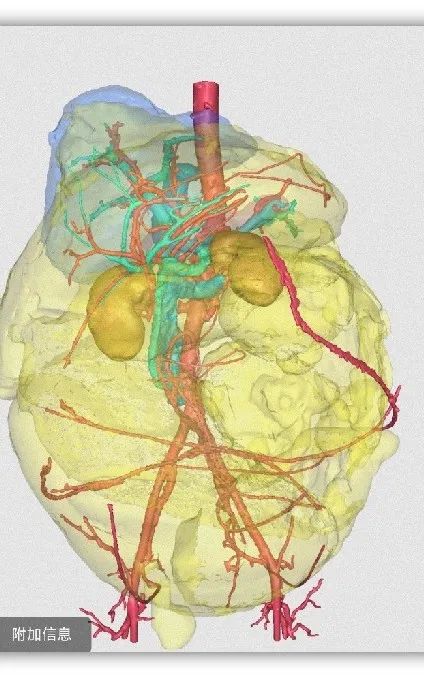

三维重建

考虑到患者肿瘤巨大,其腹围达到119cm,占据全腹腔和盆腔,暴露十分困难;重要脏器和血管均有明显推挤移位,没有正常解剖结构,手术风险极大,易造成副损伤;肿瘤生长时间长,侵及腹腔多脏器,与腹部大血管、神经、输尿管、胃肠道关系紧密,需要行多脏器联合切除,手术难度极大。经与家属充分沟通后,团队最终决定“以血管为导向”,行根治性“腹膜后巨大肿瘤切除+左肾切除+降结肠切除+肠肠吻合术”。

3月11日,老李被推进手术室。岳树强教授、刘正才副教授、李霄副主任医师等精准施术。术中探查结果和术前腹部影像、三维重建影像资料,均证实患者腹部脂肪肉瘤同样起源于左肾脂肪囊。

时间一分一秒流逝,在团队默契协作下,难题逐个攻破。患者左侧腹膜与肿瘤黏连,团队小心游离,采用线手套将肿瘤整体推向左侧,显露右侧根部并寻找血管边界,继而以重要大血管为指引,显露、解剖、裸化“下腔静脉、腹主动脉、左肾动静脉”至左右侧髂血管,最终完整切除肿瘤,手术历时4小时45分钟顺利结束。术中出血仅1700ml,输注RH+B型去白细胞悬浮红细胞10U、病毒灭活冰冻血浆1350ml。